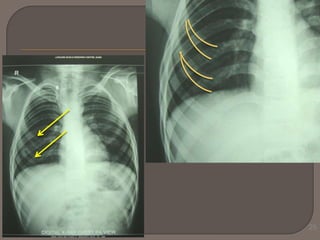

Malunion of fractured segments